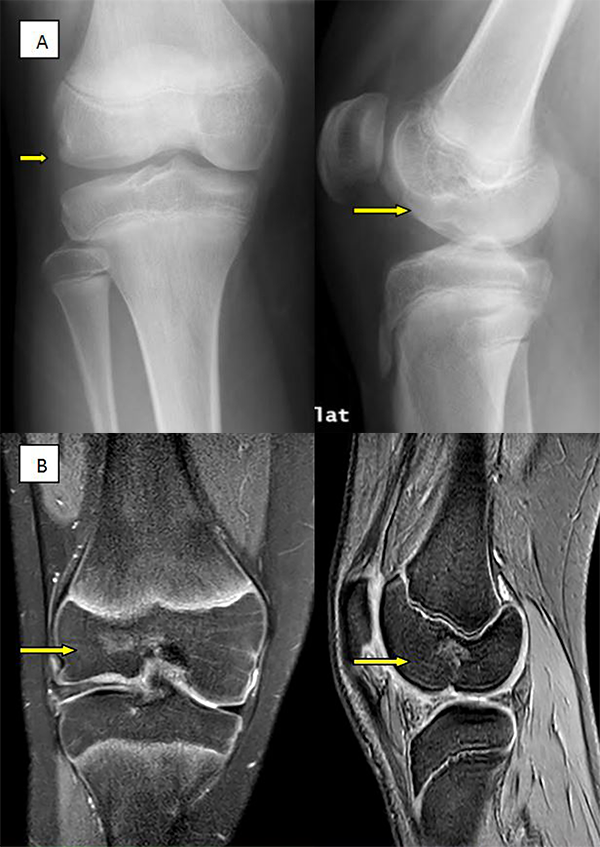

Después de 8 años de seguimiento, el paciente se encuentra asintomático, realizando vida normal, incluso deportiva. En la exploración física destaca como secuelas: dismetría del miembro inferior lesionado con 12 mm más largo y pérdida de últimos grados flexión, sin repercusión funcional (fig. 3). Las imágenes de control evolutivo del TAC y RNM demuestran una mejoría de los defectos óseo y cartilaginoso en cóndilo femoral externo (figs. 4 y 5).

Figura 5:

Control evolutivo por imágenes a los 8 años de seguimiento. A) Rx frente a la izquierda y perfil a la derecha persiste imagen lesión osteocondral con signos remodelado. B) Corte coronal de RNM a la izquierda y sagital a la derecha, mostrando mejoría en el defecto cavitario óseo y disminuyendo el tamaño de la lesión condral respecto a controles previos, con superficie condilar aplanada.